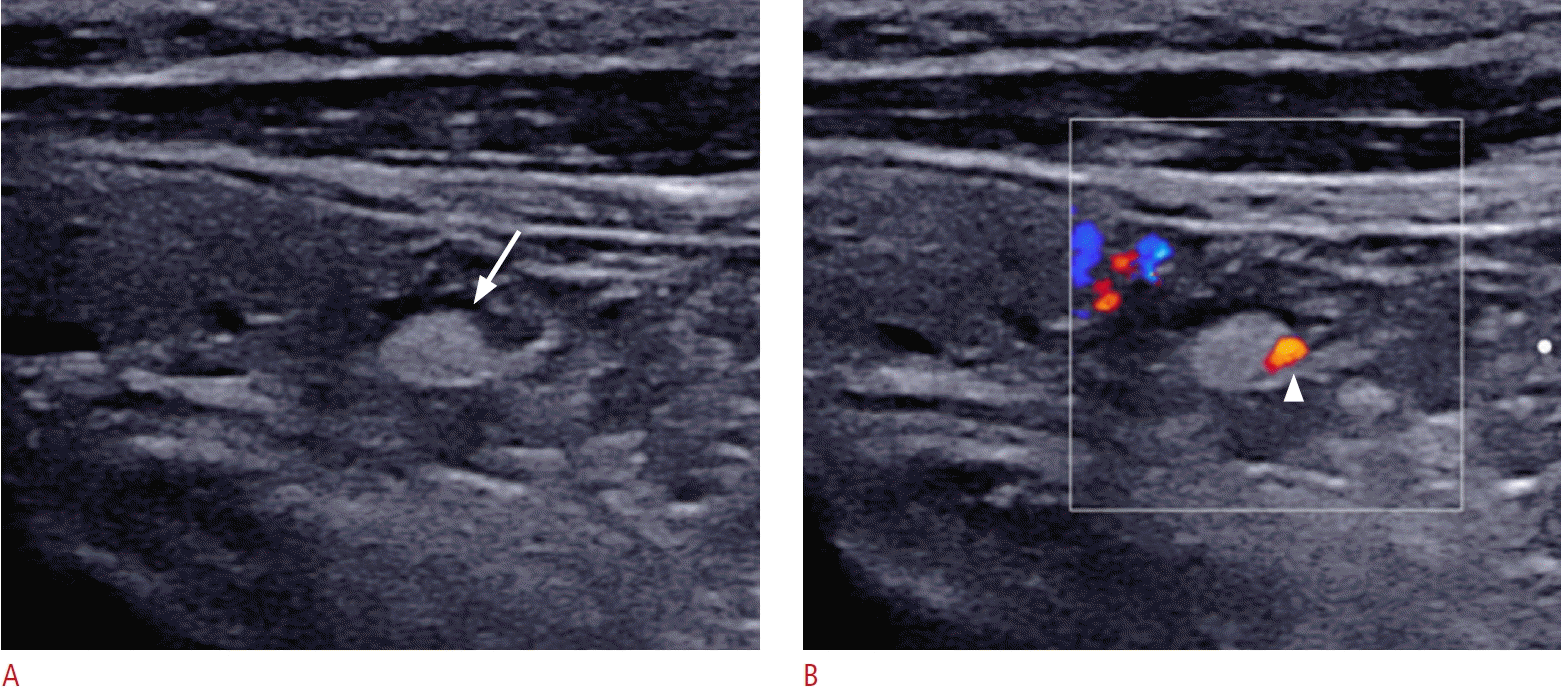

43. Wolf RJ, Cronan JJ, Monchik JM. Color Doppler sonography: an adjunctive technique in assessment of parathyroid adenomas. J Ultrasound Med. 1994; 13:303–308.

44. Huppert BJ, Reading CC. Parathyroid sonography: imaging and intervention. J Clin Ultrasound. 2007; 35:144–155.

35. Kim SJ, Paik W, Lee JC, Song YJ, Yoon K, Noh BJ, et al. Ultrasonographic features of normal parathyroid glands confirmed during thyroid surgery in adult patients. Ultrasonography. 2024; 43:364–375.

37. Kim SJ, Na DG, Noh BJ. US features of normal parathyroid glands: a comparison with metastatic lymph nodes in thyroid cancer. Ultrasonography. 2023; 42:203–213.

40. Reeder SB, Desser TS, Weigel RJ, Jeffrey RB. Sonography in primary hyperparathyroidism: review with emphasis on scanning technique. J Ultrasound Med. 2002; 21:539–552.